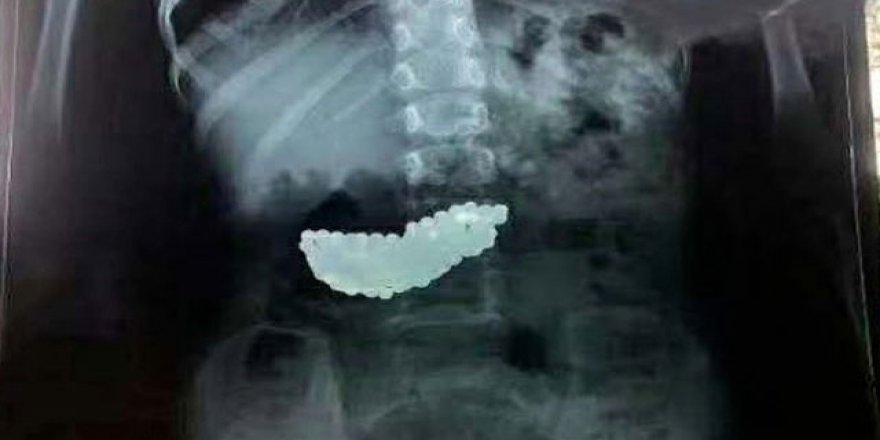

Çin'de 5 yaşındaki çocuk 190 bilyeyi 2 ay boyunca midesinde taşımış

Çinli 5 yaşındaki bir çocuğun midesinde 190 biye ile 2 yaşadığı ortaya çıktı.

Çin’in Shandong bölgesinde meydana gelen olayda, küçük kızın ailesi, bilyeleri çocuklarının oynarken yuttuğunu ve zamanla doğal yollardan dışarı atıldığını sandıklarını ifade etti.

Mıknatıslı olan bilyeler çocuğun midesinde biraraya gelerek büyük bir kitle haline geldi. Bilyeler doğal yollardan çıkmayınca küçük kız 2 ay bu kitleyle yaşadı. Doktorlar rontgenle tespit ettikleri kitleyi ameliyatla çıkardı.